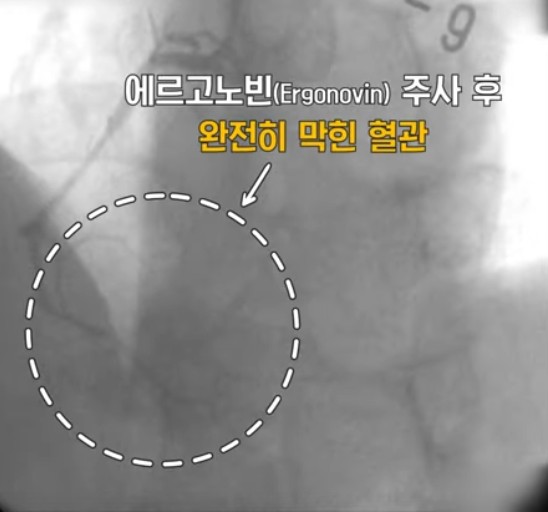

변이형 협심증(variant angina)은 심장에 혈액을 공급해 주는 관상동맥이 수축 즉 경련을 하면서

일시적 혈류 차단에 의해 가슴 통증과 무거운 것에 짓눌리는 압박감 느낌이 나는 증상이 나타는데요.

자극이 없어지면 혈관은 다시 정상을 회복하는데 마치 자다가 근육에 쥐가 났다가 풀리는 증상과 비슷하다고 합니다.

변이형 협심증을 진단하기 위해서는 경련유발검사를 시행하며 치료는 약물 치료로 대부분 증세 없이 지내실 수 있지만 대게 1년 이상 투약이 필요하고 일부 환자는 투약을 줄이거나 , 투약을 중지하는 경우도 있습니다만 평생 복용해야 하는 경우도 있습니다.

문제는 혈관이 수축(경련)하는 상태가 지속되면 급성 심근 경색증, 부정맥등의 합병증이 생기고 급성 심정사로 이어질 수 있기 때문에 위험요인이 있으시는 분은 정확한 진단과 치료를 받으시고 정기적인 검사를 하는 것이 치료와 예방에 아주 중요합니다.